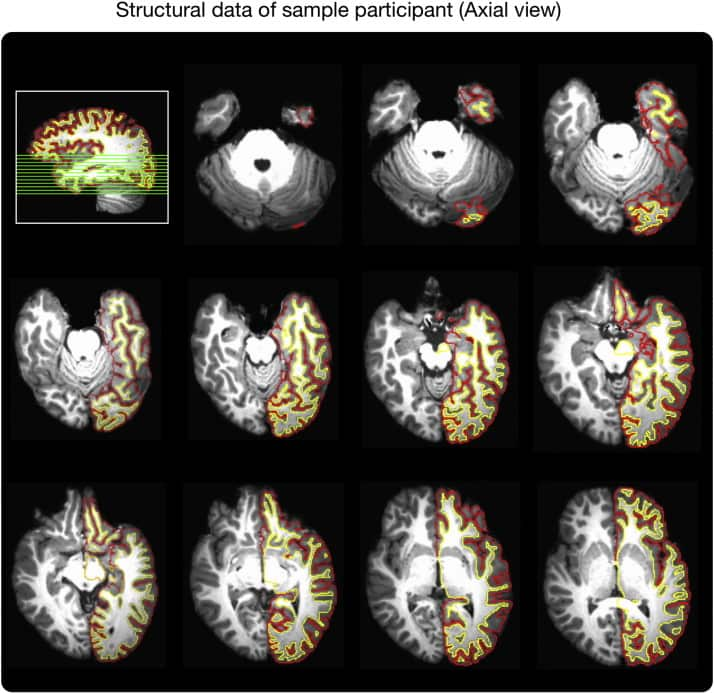

What he and his research team found was massive grey matter density and cortical thickness increases in Pandit brains in language, memory and visual systems.

"In the cerebellum -- which is the back lower part of the brain which coordinates both your motor and your cognitive functions -- we found that 33 percent of the Pandits' cerebellum grey matter was denser or more increased compared to the [other participants], which was remarkable."

"We had never seen any studies that showed such a large increase in the Hippocampus and this is incredibly important for understanding how memory works in the brain." he told SBS Hindi.